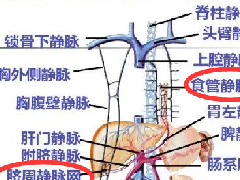

5、肿瘤血管征:可见较多粗细不一的肿瘤血管。肿瘤以外肝实质一般无明显异常,瘤周可见受压弯曲的肝血管影,主要为肝静脉和门静脉。

2) 肝细胞癌患者发病多大于3岁, 检查AFP水平升高,多与肝炎或肝硬化有关,CT表现为肿物多为形态各异,包膜不完整,边界模糊,同时病灶周边还有各种大小不一子灶。CT动态增强多为“快进快出”。同时,脂肪肝或肝硬化也是鉴别重要证据;,肝细胞癌的门脉侵犯较肝母细胞瘤多见,癌栓的形成也较多见,而肝母细胞瘤周围的血管常是受压性改变。肿瘤以外的肝脏可有脂肪肝、肝硬变 等表现也是鉴别点之一。